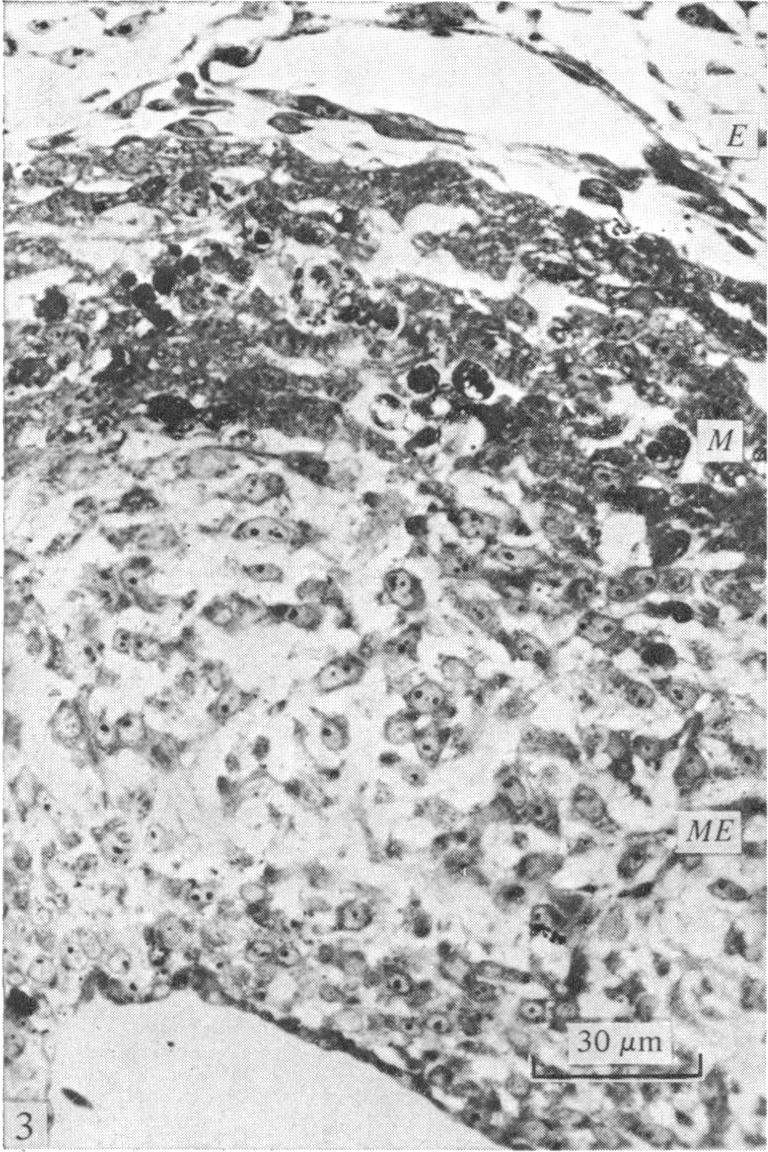

The presence of cell death in the walls of the truncus and conus of the developing chick heart was investigated by a variety of light and electron microscopic techniques. Necrotic areas were observed in the myocardial layer of the truncus and conus and within the mesenchymal cells of the truncoconal ridges and aortopulmonary septum. These necrotic zones appeared first at Stage 25-26 and reached their maximum extent at Stages 29-32 undergoing later progressive disappearance. The morphological changes of the degenerating cells detectable under both transmission and scanning electron microscopy are also reported. The possible role of cell death in the morphogenesis of the truncus and conus is discussed.